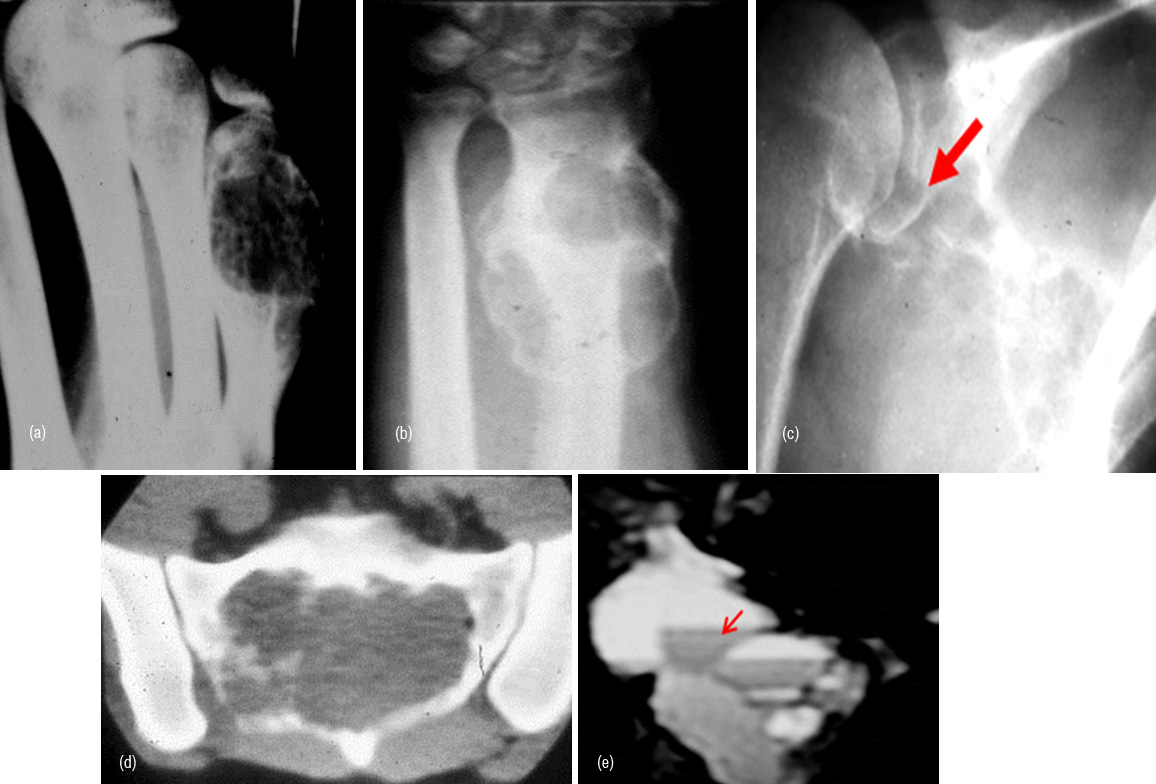

Aneurysmal bone cyst (ABC)

Primary ABC is radiologically an expanding lucent lesion with thin transitional zone located in diametaphyseal or diaphyseal area. It is encountered generally in young age but it also may be seen in adults. Pathological fractures may occur. A thin shell of bone is often noted (Figure 8abc). In spine, it may involve the body/pedicle/spinus process of vertebra (Figure 8d). In CT/MRI fluid fluid levels may be noted (Figure 8e). However, fluid fluid levels may also be seen in other lesions such as giant cell tumor. A solid variety of ABC is also seen and pathologists consider this as a variant of giant cell reparative granuloma which often occurs in the bones of hand and face.

Figure 8: ABC, (a) 5th metacarpal, (b) Radius, (c) Scapula, (d) Sacrum may simulate giant cell, (e) Fluid fluid levels in ABC (MRI).